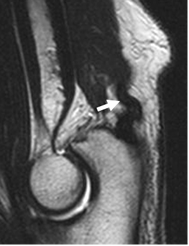

En la ecografía los tendones se identifican como estructuras hipoecoicas, con un patrón fibrilar y en relación con los sitios de origen o inserción. (Fig 15 y 16).

Fig 15. Tendones normales en ecografía.

A: Vista longitudinal, sobre la inserción del tendón del bíceps.

B: Inserción del tríceps, en vista longitudinal.